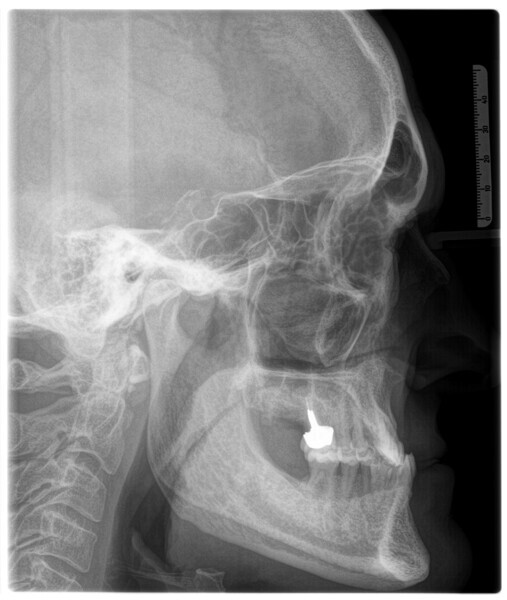

The 58-year-old patient wished to improve his oral aesthetics and function, complaining of mobility of the posterior teeth and wear of the anterior teeth. After data collection, a very complex situation was identified (Figs. 11–13):

1. severe periodontitis with poor prognosis of some teeth;

2. anterior crossbite;

3. severe wear mainly of the anterior teeth and compensatory eruption;38

4. atypical swallowing and lower posture of the tongue at rest;

5. masticatory dysfunction during the mastication test; and

6. no significant signs of temporomandibular disorder.

For maintenance purposes, after prosthetic finalisation, the patient was to carry on with the Froggymouth therapy and to use the Ri.P.A.Ra. for physiotherapeutic exercises and mastication training (Fig. 28). It was strongly recommended that the patient wear a mandibular occlusal splint during sleep. This occlusal splint was designed with disclusion guides to advance the mandible and ensure balanced contralateral support (Fig. 29).11, 39 We achieved an aesthetic appearance with adequate inter-arch coherence and a better cephalometric result (Figs. 30 & 31).